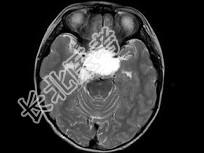

- 单项选择题女,8岁, 头痛、左侧肢体麻木十余天,根据所提供图像, 最可能的诊断是 ( )

A、表皮样囊肿

B、颅咽管瘤

C、垂体瘤

D、胶质瘤

E、蛛网膜囊肿